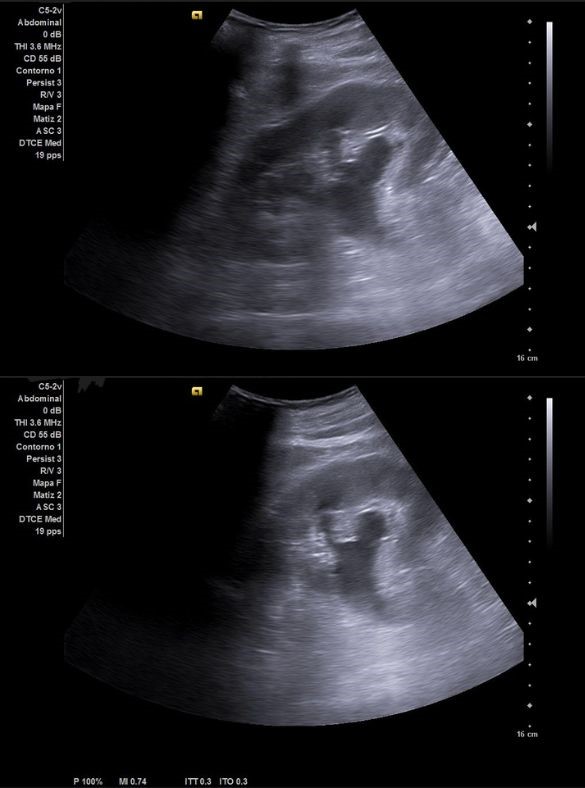

Ecografía venosa: venas femorales y poplíteas permeables. A nivel inguinal se observa imagen heterogénea, mal definida, sospechosa de malignidad.

Ecografía clínica urológica: se objetiva vejiga muy distendida hasta epigastrio con imagen heterogénea en pared posterior de vejiga de gran tamaño que capta al Doppler color sospechosa de malignidad. Con signo de hidronefrosis riñón izquierdo grado III.